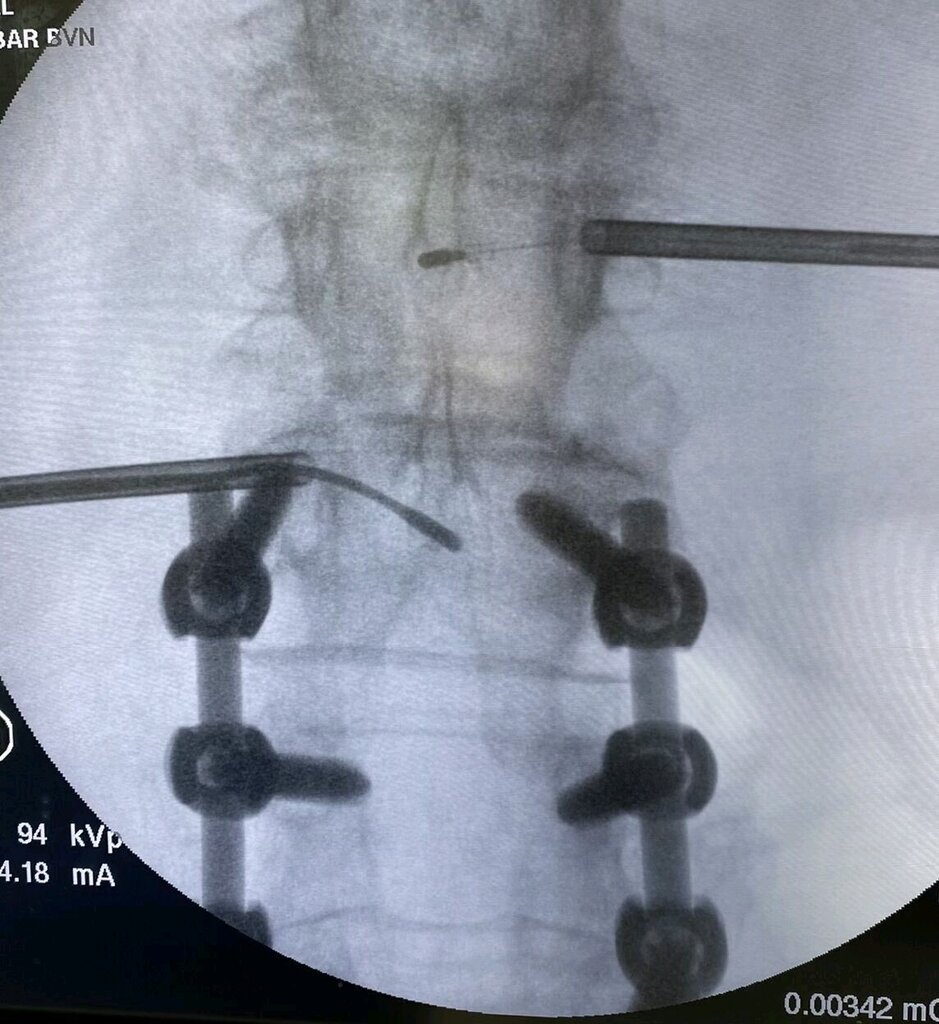

I have an otherwise ideal candidate for this at L45, failed all else reasonable, who has L2-4 fusion with pedicle screws. I don’t think I have the balls to do my first ever extrapedicular access for anything ever. He is fully fused on CT scan and no motion on x-ray… his surgeon is willing to remove an L4 screw so I can do this

If you must try this just go extra pedicular. Think of where your target is and where the bad stuff lies and ignored the screw. It’s not hard to get there. So long as you have a small patient or a long needle

Don’t remove the screw. That makes a little case, big. It is safer and easier going extrapedicular.

If you can intentionally narrowly miss) the medial wall of the pedicle (which is what you are doing with the traditional approach you can guide a trochar in high and outside. I know you can do it. Do you have any seasoned kyphon reps you can talk to? We could have Doug Beall on FaceTime for you too during the case even. He is a consultant for them.

Since it is bipolar there shouldn’t be any inadvertent transfer. If the edge of a pedicle screw is at the Edge of the burn zone I don’t think it should transfer to the canal or root. The hardware should be insulated by bone from these structures.

I would leave the screw but also have never gone around them myself. Seems like on DocMatter several have reported no issues with heating. Do you have any images? Would be interesting to see the approach.

Not sure when you are doing the case, but next month the 7 minute smaller 5mm radius burn will officially be released, so that would likely keep heat further from screws.

Doug Beall going over the top of screw